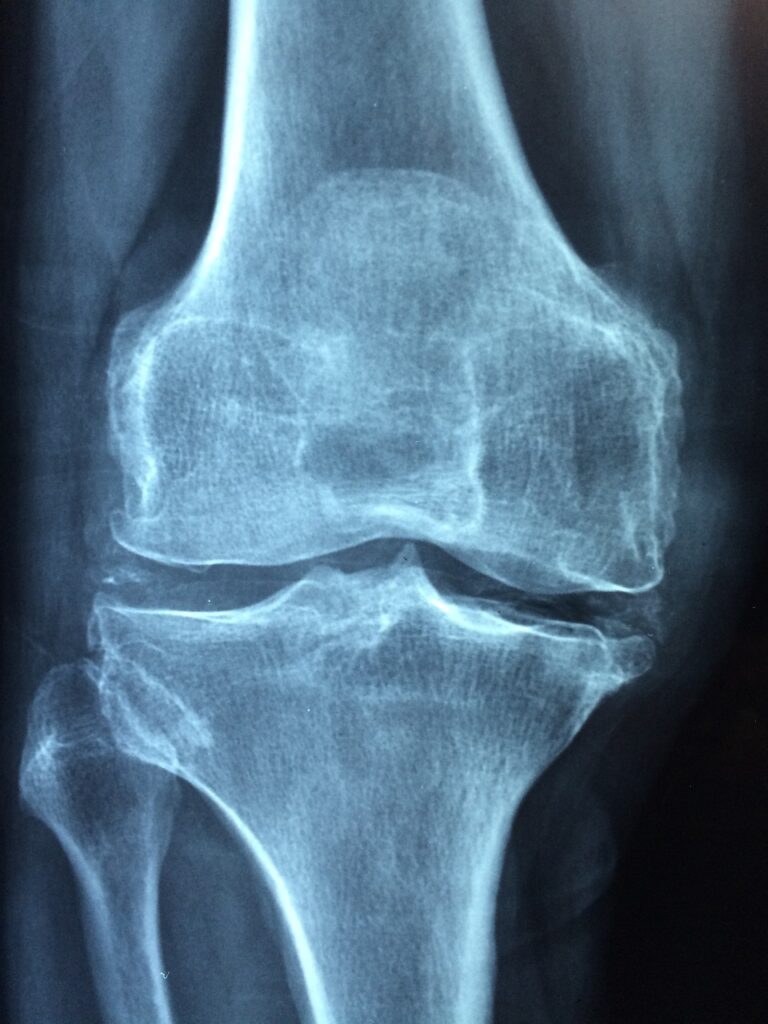

"Radi se o "tihoj epidemiji" jer je bolest asimptomatska. Prvi simptomi se jave kada dođe do posljedica - patoloških prijeloma. Pod pojmom osteoporoze smatramo skeletno oboljenje koje se karakteriše smanjenjem gustoče kostiju koja zapravo nastaje usljed smanjenja kalcija i kosti postaju porozne, često se lome i imamo posljedicu patološki prijelom. Osim boli koja je evidentna, dolazi do invaliditeta osobe i smanjuje se kvalitet života. Postoji čitav niz riziko faktora koji dovode do nastanka oboljenja i ukazuju na ozbiljnost, ali se do 1994. godine osteoporoza nije smatrala značajnom bolešću već fiziološkim stanjem koje se smatralo posljedicom starenja. Tek 1998. godine formiranjem Svjetske fondacije za osteoporozu na globalnom nivou se podiže svijest o značaju ovog oboljenja", kazala je za N1 prof.dr. Hasanović.